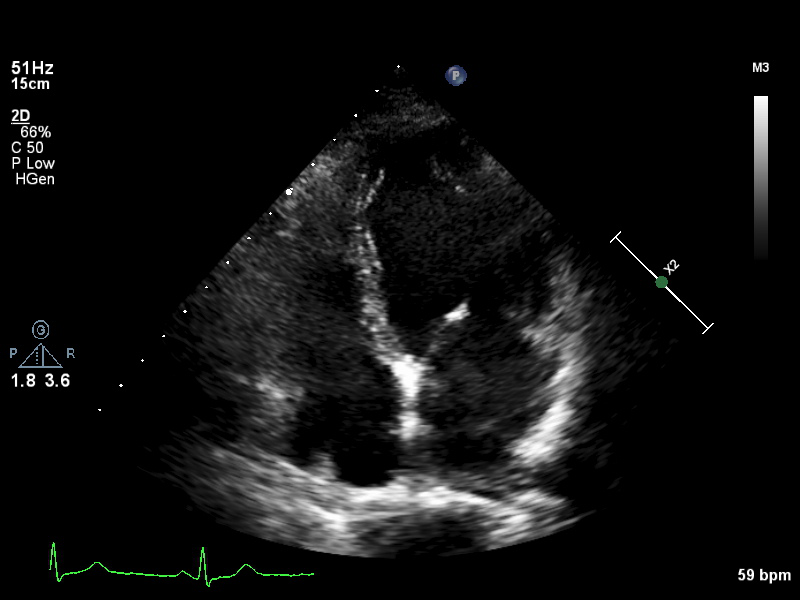

a4ch-full a4ch-full Apical 4-chamber showing the full depth of all four chambers (no LV/RV focus)

a4ch-ias a4ch-ias Apical 4-chamber, focused on the inter-atrial septum

a4ch-la a4ch-la A4CH with Doppler near MV/LA or 2D covering full LA, not full LV

a4ch-lv a4ch-lv A4CH covering the whole depth of the LV, not the whole depth of the LA

a4ch-ra a4ch-ra Apical 4-chamber focused on the right atrium, or colour Doppler on TV/RA

a4ch-rv a4ch-rv Apical 4-chamber focused on the right ventricle